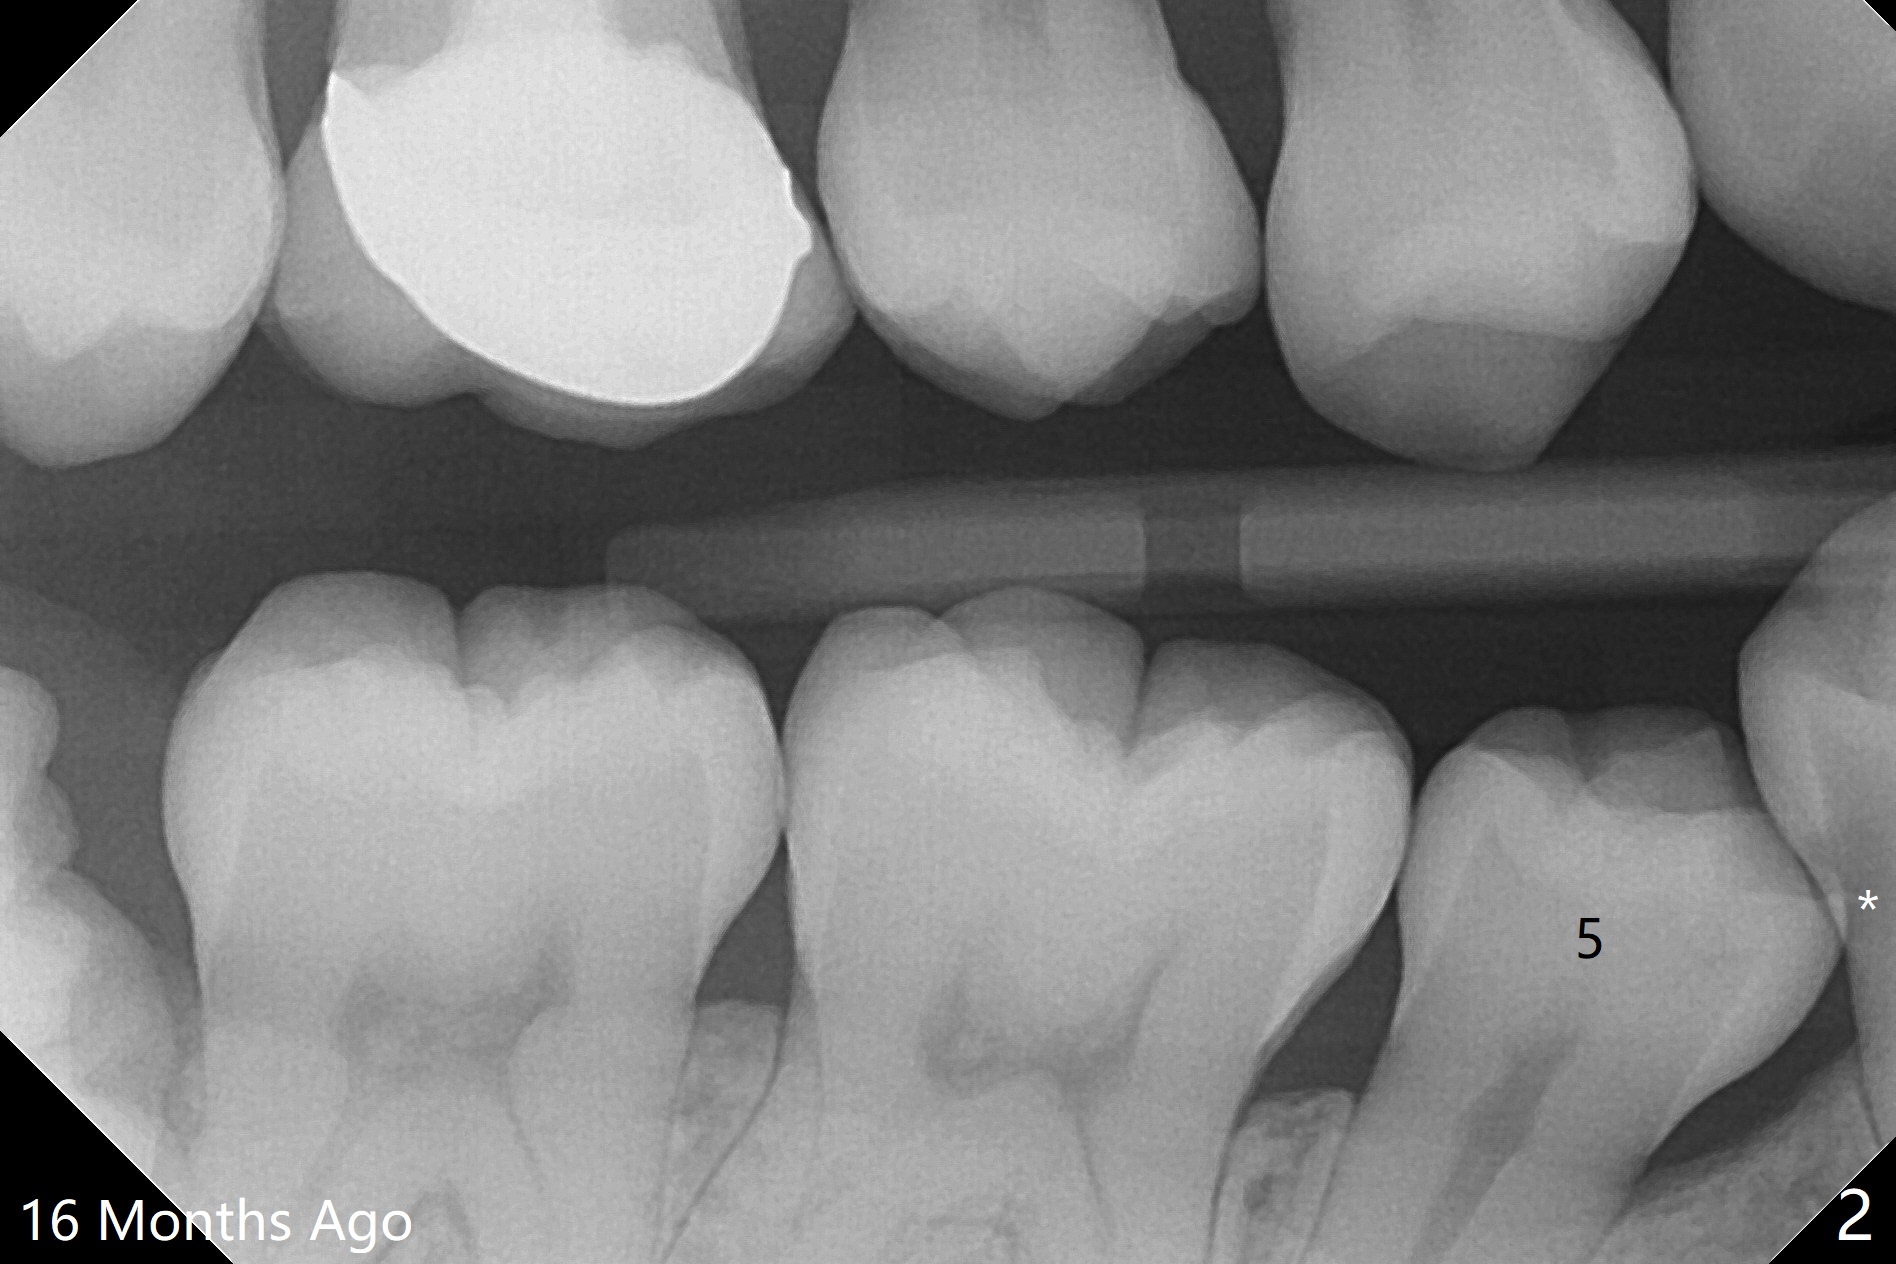

A 34-year-old woman with crowding particularly at LR 4/5 (Fig.1) and suspected DO caries of LR4 (Fig.2) returns with symptom of pulpitis and "cavity" at LR5 (MO). New Bitewing confirms LR4 DO caries (Fig.3). Treatment plan is to extract LR4 and place composite at LR5 if present. Extraction turns out to be difficult because of nervousness and TMD of the patient and crowding. The proximal areas of LR4 requires removal before luxation without traumatizing the neighboring teeth (Fig.4 insert black areas). In fact there is no caries at LR5. When the patient returns for orthodontic treatment, bracketing at LR5 should consider overcorrection (Fig.5 (black rectangle vs. red line: height of contour)) due to the tilted long axis (Fig.1).